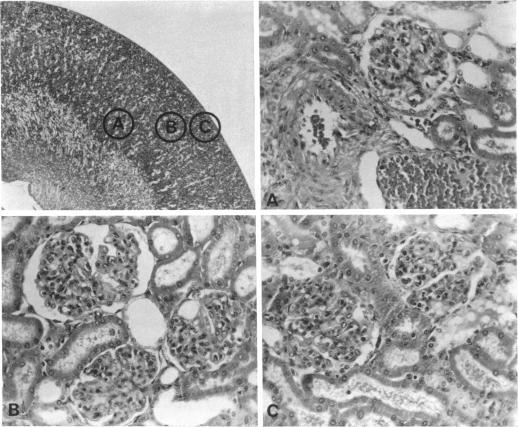

Micropuncture, clearance, immunofluorescence and light microscopy techniques were used to study kidney structure and single nephron function in rats with autologous immune complex nephritis (AICN), a membranous glomerulonephritis developing over 5 to 20 mo, in the more acute and proliferative glomerular basement membrane (GBM) nephritis and in controls. Both models are known to have clinical counterparts in human disease. Kidney functional abnormalities correlated with the degree of architectural derangement. In both AICN and anti-GBM nephritis filtration fraction fell in direct proportion to the fall in glomerular filtration rate (GFR), renal plasma flow being unchanged. Fractional electrolyte excretion increased as the GFR fell. Despite marked heterogeneity of single nephron filtration rate (SNGFR) (AICN, 5-93 nl/min; anti-GBM, 0-50 nl/min) and of proximal tubular hydrostatic pressure (4-48 mm Hg), each nephron showed almost complete glomerulotubular balance, absolute reabsorption to the late proximal convolution varying directly with filtration rate. In addition SNGFR could be related both to proximal intratubular hydrostatic pressure and to calculated glomerular capillary pressure (Pg), being lowest in those nephrons with the highest intratubular pressure. Nephrons with very high filtration rates did not apparently reach filtration equilibrium. Mean SNGFR was significantly lower in the anti-GBM group, while calculated Pg was the same in both. This probably reflects the acute and diffuse involvement of the anti-GBM lesion with different filtration characteristics from the more chronic AICN disease. Tubular damage was more marked in AICN, and extraction of p-aminohippurate was reduced in this group.

采用微穿刺、清除率、免疫荧光和光学显微镜技术,对患有自体免疫复合物肾炎(AICN)的大鼠的肾脏结构和单肾单位功能进行研究。AICN是一种在5至20个月内发展的膜性肾小球肾炎,在更急性和增殖性的肾小球基底膜(GBM)肾炎以及对照组中进行研究。已知这两种模型在人类疾病中都有临床对应物。肾脏功能异常与结构紊乱程度相关。在AICN和抗GBM肾炎中,滤过分数均与肾小球滤过率(GFR)的下降成正比,肾血浆流量不变。随着GFR下降,电解质排泄分数增加。尽管单肾单位滤过率(SNGFR)(AICN为5 - 93 nl/min;抗GBM为0 - 50 nl/min)和近端肾小管静水压(4 - 48 mmHg)存在明显异质性,但每个肾单位几乎都表现出完全的球管平衡,近端曲管后期的绝对重吸收与滤过率直接相关。此外,SNGFR既与近端肾小管内静水压有关,也与计算出的肾小球毛细血管压(Pg)有关,在肾小管内压力最高的那些肾单位中最低。滤过率非常高的肾单位显然未达到滤过平衡。抗GBM组的平均SNGFR显著较低,而两组计算出的Pg相同。这可能反映了抗GBM病变的急性和弥漫性累及,其具有与更慢性的AICN疾病不同的滤过特征。AICN组的肾小管损伤更明显,该组对对氨基马尿酸的摄取减少。